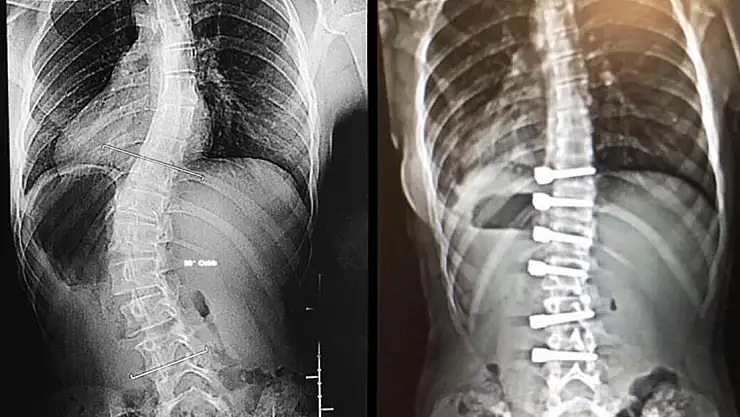

Skolyozda görülen çocuktaki hafif değişikliklerin aile üyesi, yakın bir arkadaş ya da öğretmen tarafından fark edilebileceğini vurgulayan Dr. Ulaş, bu durumda mümkün olduğunca hızlı bir şekilde bir hekime başvurulması gerektiğine dikkat çekti. Skolyoz cerrahisinde amacın eğilmiş omurları düzgün bir şekilde dizip birbirine kaynatmak olduğunu dile getiren Ulaş, "Kaynama sonrasında bu bölge tek bir kemik (omur) gibi hareket eder. Genelde 45-50 derecenin üzerinde olan eğrilikler ergenlik bitip büyüme tamamlansa bile ilerlemeye devam eder. İlerleme sırtta ve belde estetik olarak kötü bir görüntü oluşturduğu gibi akciğer fonksiyonunu da bozabilir. Bu durumda skolyoz cerrahisi yapan çoğu doktor skolyoz eğriliğini azaltmak ya da artmasını engellemek için cerrahi tedaviyi tercih eder. Günümüz teknolojisi skolyoz cerrahlarının eğrilikleri düzeltebilme yeteneklerini artırmıştır. Böylece estetik olarak düzgün bir görüntü elde edilebilir. Eğrilmiş omurların birbirine kaynatıldığı füzyon ameliyatı, skolyoz eğriliğinin artmasını engellemekte çok başarılıdır" ifadelerini kullandı.

“Skolyoz eğriliği ne kadar esnekse o kadar çok düzelir”

Ameliyattan önce özel eğilmeli ya da traksiyon filmi denilen özel röntgen filmleriyle skolyoz eğriliğinin ne düzeyde esnek olduğunun anlaşılmaya çalışıldığını vurgulayan Dr. Ulaş şunları söyledi: "Ameliyatı yapacak olan cerrah bu filmlerle ölçüm yaparak esneklik hakkında fikir sahibi olur. Skolyoz eğriliği ne kadar esnekse, o kadar çok düzelme elde edilir. Skolyoz ameliyatından sonra iz kalmasını engellemek için cilt estetik dikiş kullanılarak dikilir. İz oluşumunu engelleyici kremlerin kullanılması ve ilk yıl güneşe çıkarken kesi hattının üzerinin örtülmesi kullanılan diğer önlemlerdir. Skolyoz ameliyatı, omurganın tekrardan pozisyon verildiği, kasların yerlerinin değiştiği büyük bir ameliyattır. Genelde ameliyat sonrası ilk günlerde ağrı daha fazla olur. Çoğu hasta ağrısı üçüncü günden sonra azalarak hastaneden taburcu olur. Daha sonra aşamalı olarak ağrıları azalır ve genelde 2 ya da 4 hafta sonra okul çağındaki çocuklar okula gidebilirler. Hastalar ameliyat sonrası ikinci günde ayağa kaldırılıp yürütülürler."